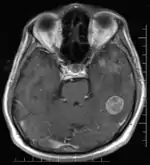

- La zone appelée SDN-POA (sexually dimorphic nucleus (SDN) dans l'aire préoptique médiane (POA), ainsi que INAH3 qu'elle comprend, située dans l'aire pré-optique de l'hypothalamus, est d'une taille significativement plus grande chez l'homme que chez la femme. "Personne ne sait encore ce que fait cet amas de cellules" reconnaît Rebecca Jordan-Young[41].

- Il existe une asymétrie cérébrale plus importante chez les hommes que chez les femmes pouvant expliquer les meilleures performances des hommes dans les épreuves visuo-spatiale[40];

- À l'inverse, il existe une symétrie bilatérale plus importante chez la femme qui pourrait rendre compte de leur meilleure performance dans le domaine verbal[40]. Une étude d'imagerie par résonance magnétique fonctionnelle menée sur des enfants s'est intéressée au traitement neuronal et a montré les différences suivantes : l’activation chez les filles bilatéralement dans les gyrus frontal inférieur, gyrus temporal supérieur et gyrus fusiforme gauche est plus grande dans les 4 tâches (jugement orthographique auditif ou visuel, jugement phonologique auditif ou visuel)[42]. En revanche, la plus grande activation dans le gyrus temporal supérieur se limite aux tâches auditives[42]. L’activation du cerveau dans le gyrus occipital inférieur et dans le gyrus temporal moyen gauche est corrélée à la performance d’exactitude dans les 2 tâches, ce qui n’est pas le cas chez les garçons[42]. Chez eux, la corrélation avec l’exactitude se fait avec la modalité de présentation du mot : pour les mots audibles, c’est la région frontale inférieure qui est activée, tandis que pour les mots visibles, c’est l’activation du lobe pariétal supérieur gauche et le précuneus qui entrent en jeu[42].